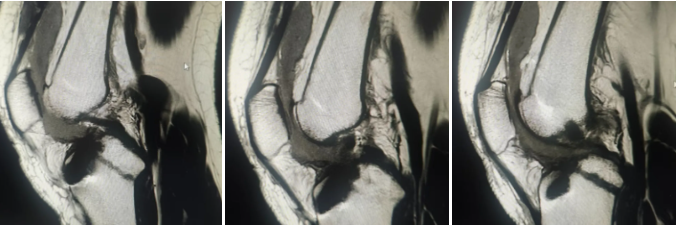

术中使用的人工韧带和手术切口

术后复查膝关节MRI检查